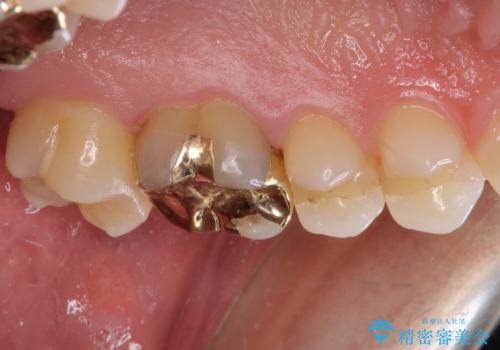

- 奥歯の詰め物が外れてしまったとのことで来院された患者様です。

幾度も詰め物治療を行ったため継ぎ接ぎだらけとなっていたため、インレーにて修復治療をすることとしました。

咬合力が強いため、ゴールド合金(PGA)のインレーを選択することとしました。